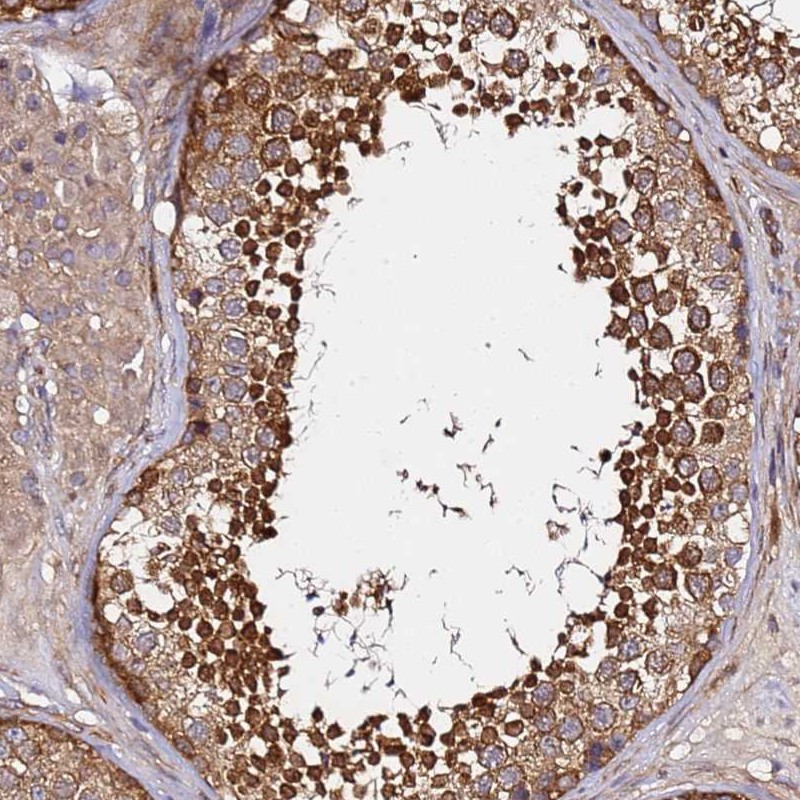

Immunohistochemical staining of human testis shows strong cytoplasmic positivity in cells in seminiferus ducts.